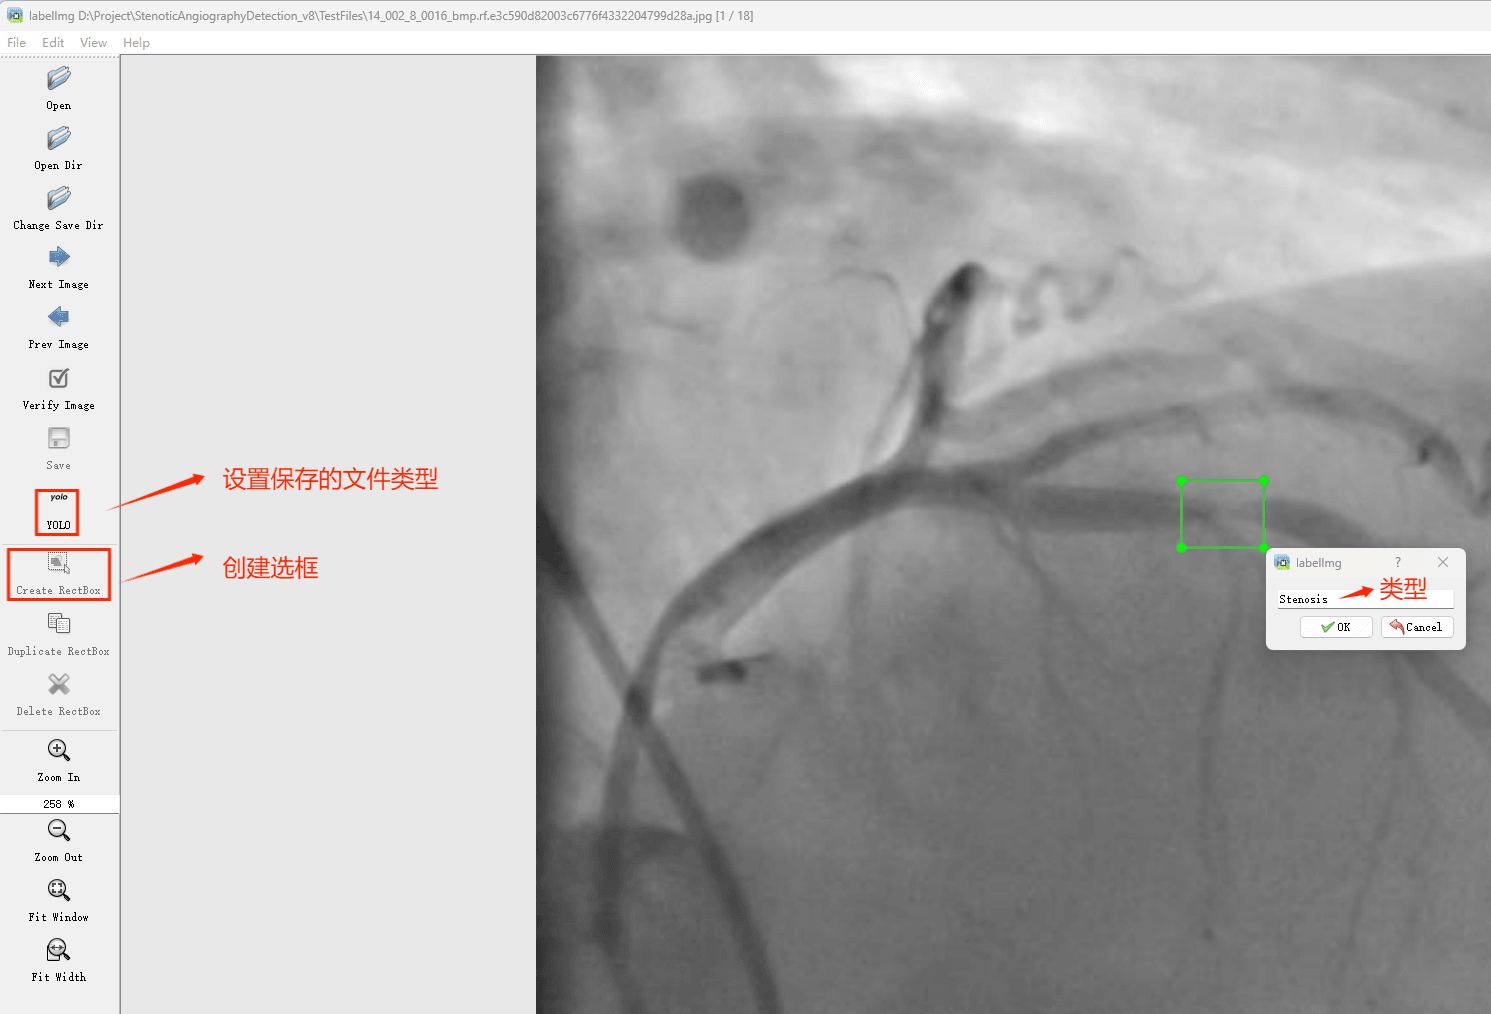

项目数据

Tipps:通过搜集关于数据集为各种各样的狭窄性血管造影相关图像,并使用Labelimg标注工具对每张图片进行标注,分1检测类别,是’狭窄性血管造影’。

目标检测标注工具

(1)labelimg:开源的图像标注工具,标签可用于分类和目标检测,它是用python写的,并使用Qt作为其图形界面,简单好用(虽然是英文版的)。其注释以 PASCAL VOC格式保存为XML文件,这是ImageNet使用的格式。此外,它还支持 COCO数据集格式。

(2)安装labelimg 在cmd输入以下命令 pip install labelimg -i https://pypi.tuna.tsinghua.edu.cn/simple

结束后,在cmd中输入labelimg

初识labelimg

打开后,我们自己设置一下

在View中勾选Auto Save mode

接下来我们打开需要标注的图片文件夹

并设置标注文件保存的目录(上图中的Change Save Dir)

接下来就开始标注,画框,标记目标的label,然后d切换到下一张继续标注,不断重复重复。